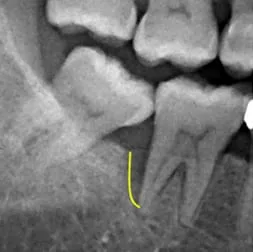

(治療前)

治療前X光片顯示說明:黑影區域為齒槽骨被牙結石及細菌嚴重侵蝕,齒槽骨被細菌侵蝕後的高度顯示出骨頭降低程度至牙根尖處。